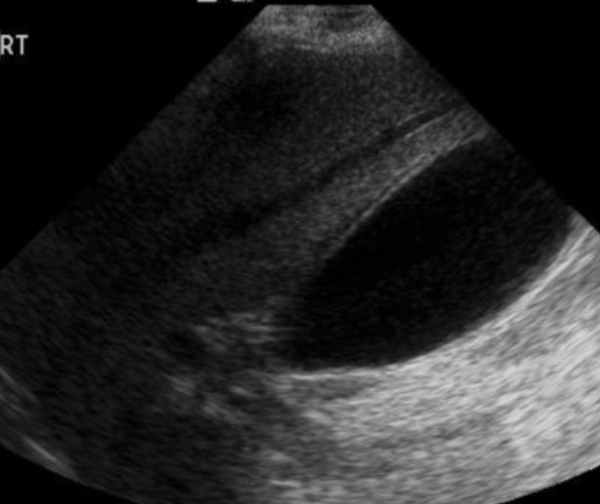

Splenic Trauma → blunt trauma usually resulting in hematoma

clinical hx: usually blunt abdominal trauma, underlying splenomegaly increased risk

s/sx: LUQ pain, low hematocrit from bleeding, abdominal swelling/bloating discomfort

2D US: capsule intact = subcapsular hematoma (conforms to spleen shape), ruptured capsule = free fluid/hematoma may form (check abdominal gutters for free fluid)

color doppler: avascular

DDX: splenic infarction, splenic abscess